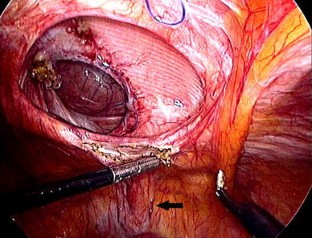

Fig. 4